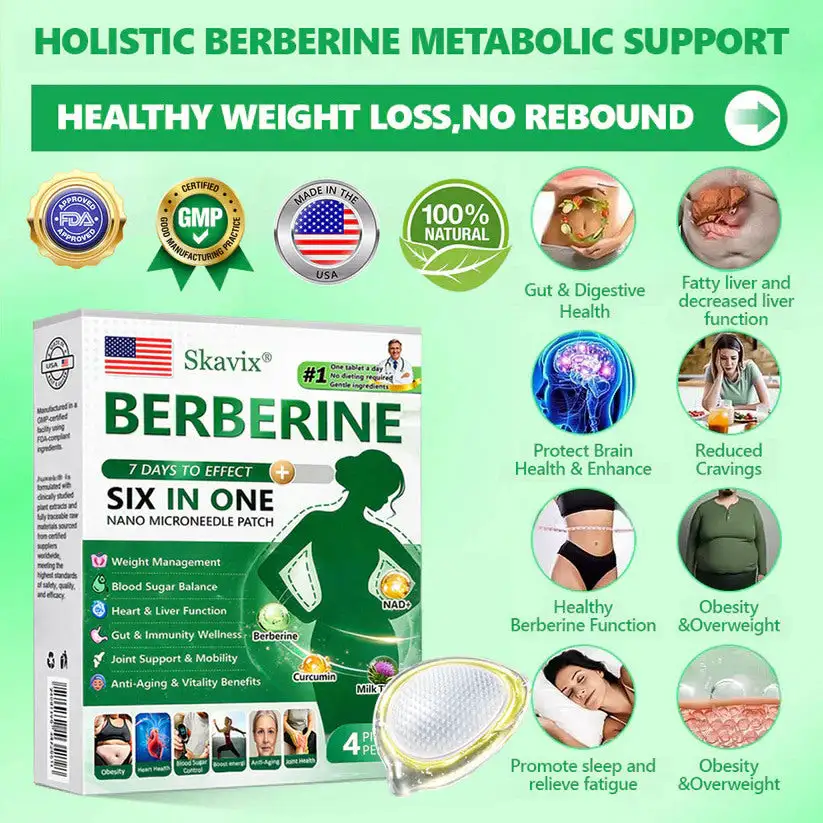

What if one simple patch a day could help you feel more balanced, refreshed, and comfortable in your everyday life — without complicated routines? That’s exactly what Skavix® Berberine 6-in-1 Nano Microneedle Patch is designed for. With advanced nano microneedle technology and carefully selected ingredients, the patch works gently throughout the day to support daily balance and overall wellbeing. Many people notice that over time they feel more refreshed, more comfortable in their body, and more confident in their daily life. Sometimes a small daily habit can make a meaningful difference.

Appetite Suppressant Advantage:

𝑩𝒆𝒓𝑏𝘦𝘳𝑖𝗇𝒆,𝑩𝒆𝒓𝑏𝘦𝘳𝑖𝗇𝒆 HCI and NAD+work continuously on thecentral nervous system. They enhance satiety signals, disrupt hunger cues, and reshapelong-term eating habits. As a result, users naturally reduce food intake,lower daily calorie consumption, and build asolid foundation for weight loss.

Metabolic Synergy:

At the cellular level, 𝑩𝒆𝒓𝑏𝘦𝘳𝑖𝗇𝒆 and moringaactivate key metabolic pathwaysin fat cells, liver cells, and skeletal muscle cells. They promote lipolysis by breaking down triglycerides into free fatty acids and efficiently transporting them to mitochondria for oxidation and energy production. They also boost basal metabolic rate, accelerating peripheral energy expenditure. This dual-action mechanism helps the body burn excess fat, leading to weight loss, while thesynergistic metabolism ensures stable results and prevents rebound.